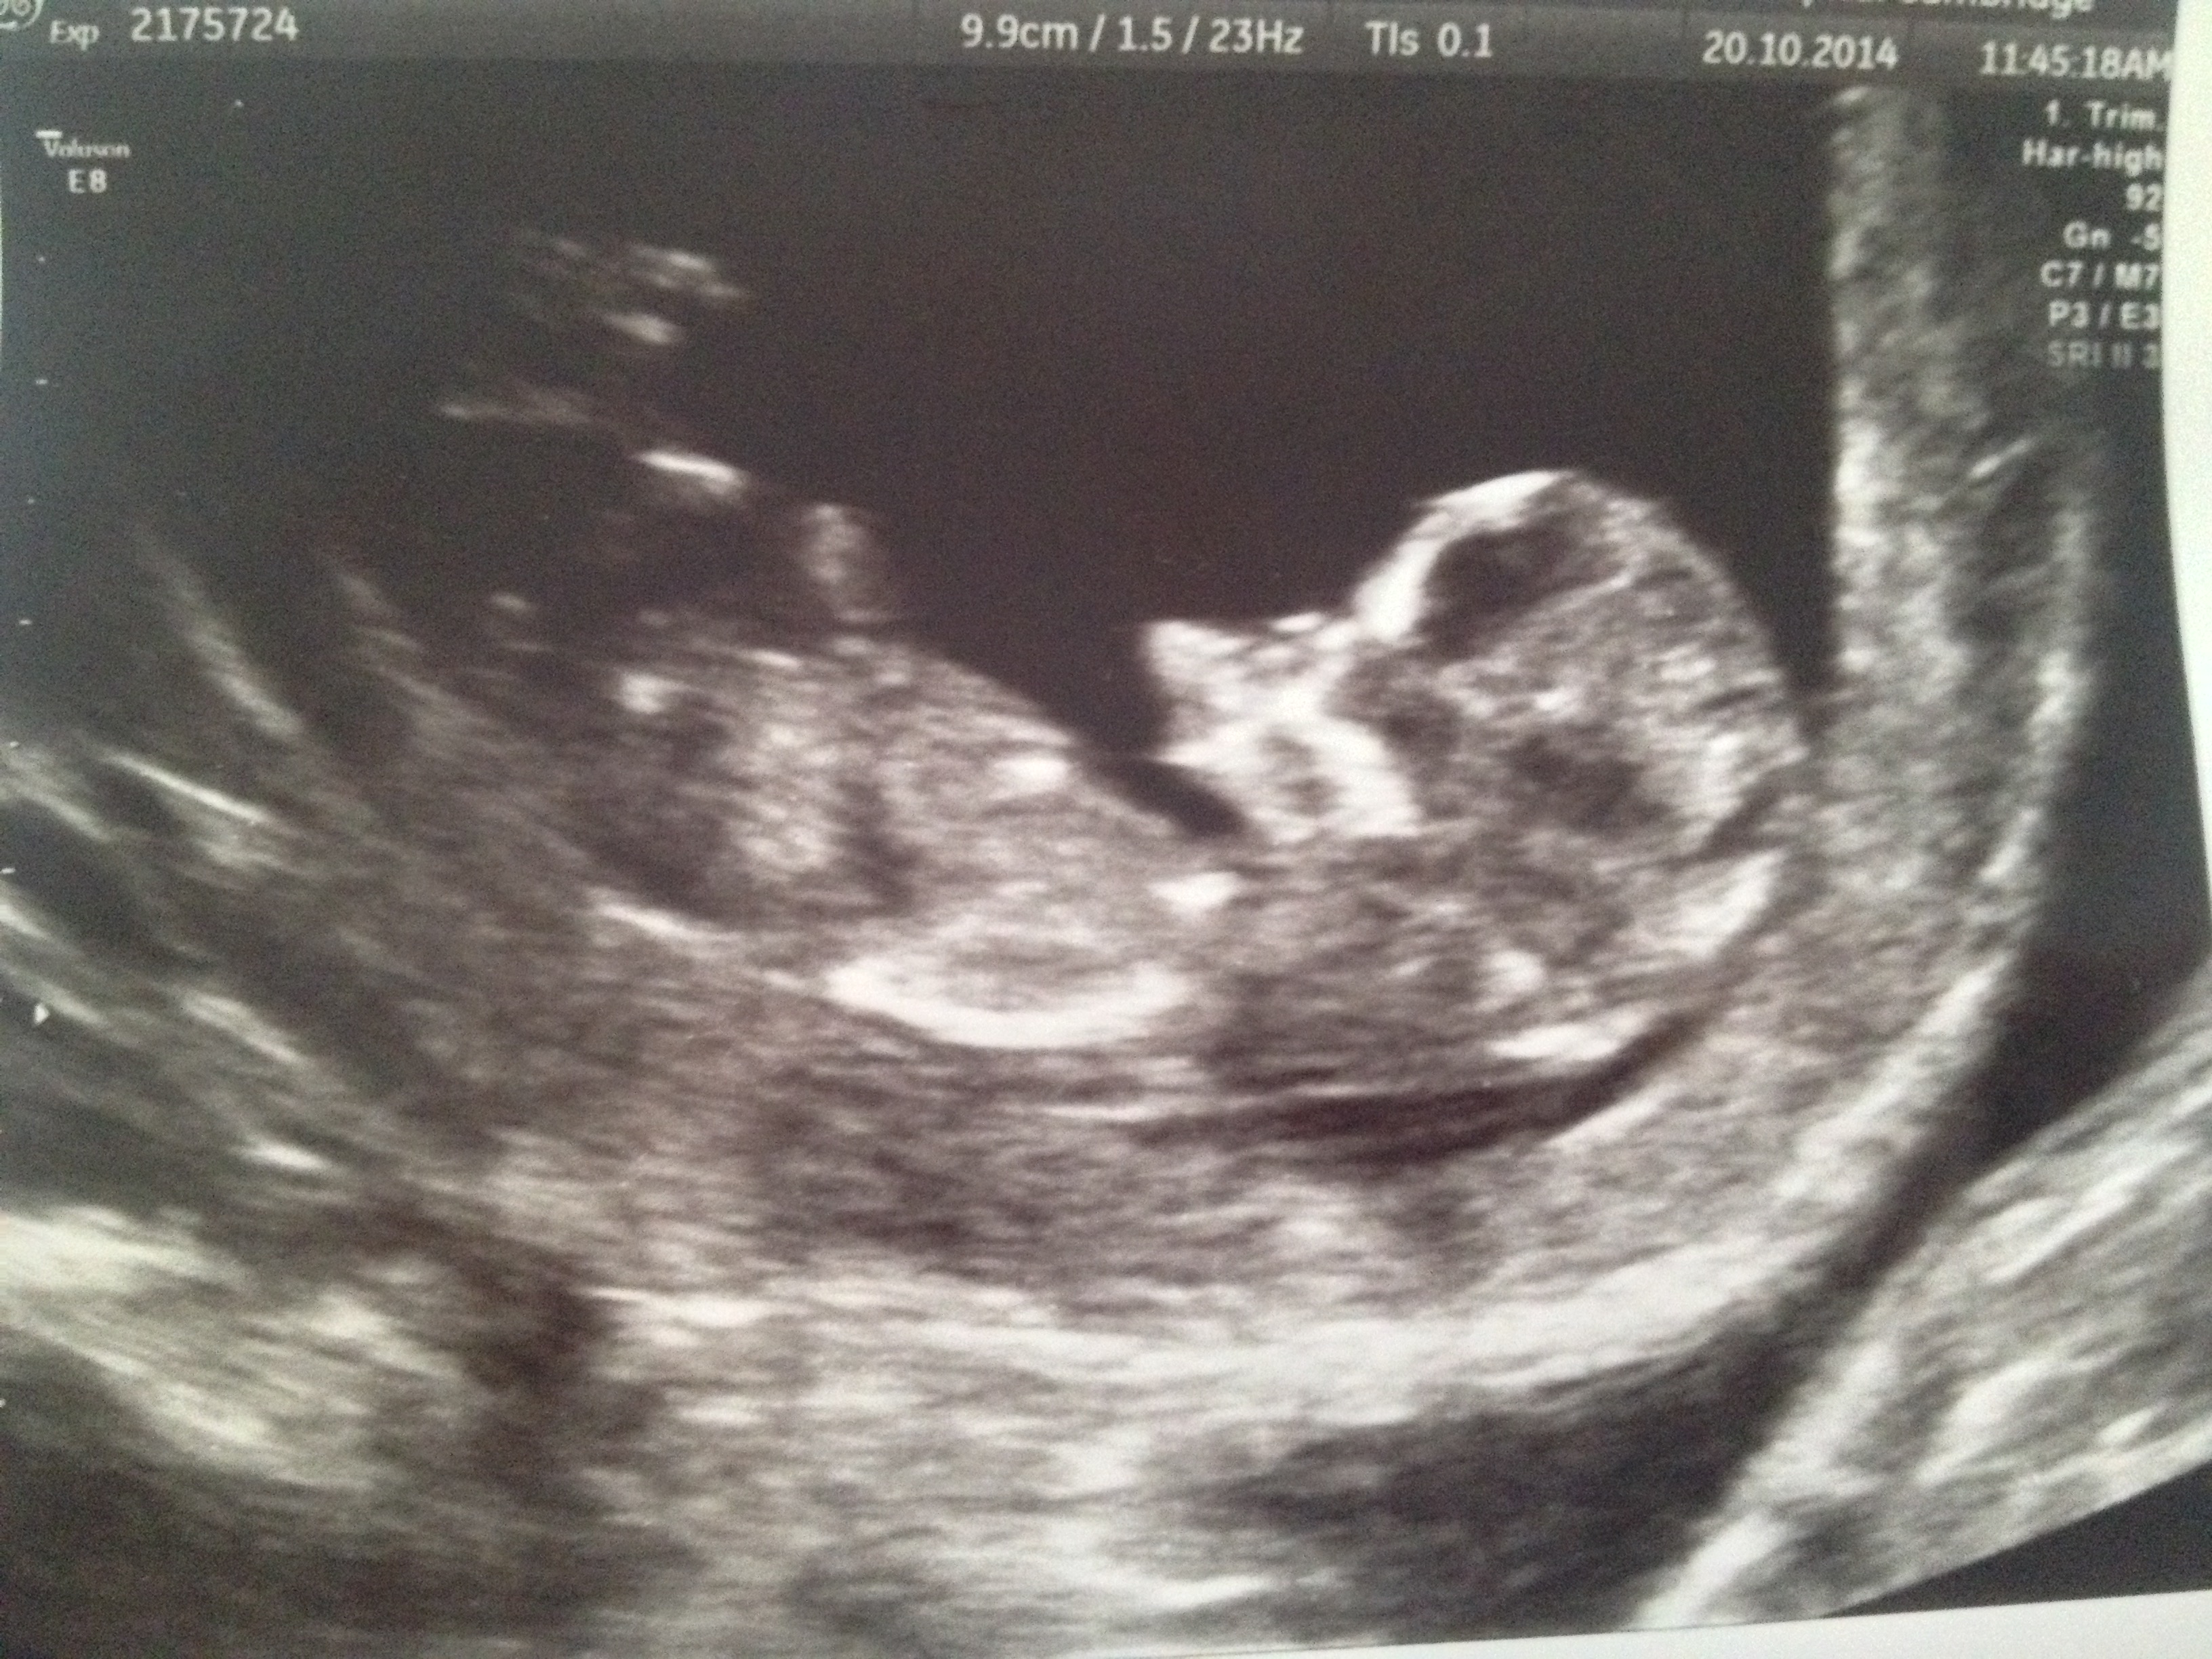

12 weeks 1 day ultrasound boy or girl?

12 weeks 1 day ultrasound boy or girl? from genderdreaming.com

How our 12 week ultrasound showed baby's gender! Missed miscarriage 12 week ultrasound. I wasn't expecting to learn the gender this early, but the. 1668 x 1798 jpeg 257 ะบะฑ. Ultrasound of 12 weeks unborn baby boy (fetal j.snow) in there, he's fetus, not embryo anymore. 12 week ultrasound.boy or girl? My boys nub looked a lot different! I know everyone says 12 weeks is too soon to tell the i've had a lot of fun looking at skull theory!

Our sonographer said we are having a boy (very excited about this!) she went off the nub theory, what do you think?